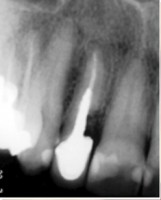

Carga Imediata após exodontia atraumática

Fatos interessantes pertinentes a este caso:

- Extração imediata

- Implante imediato

- Carga imediata

- Coroa protética cerâmica imediata